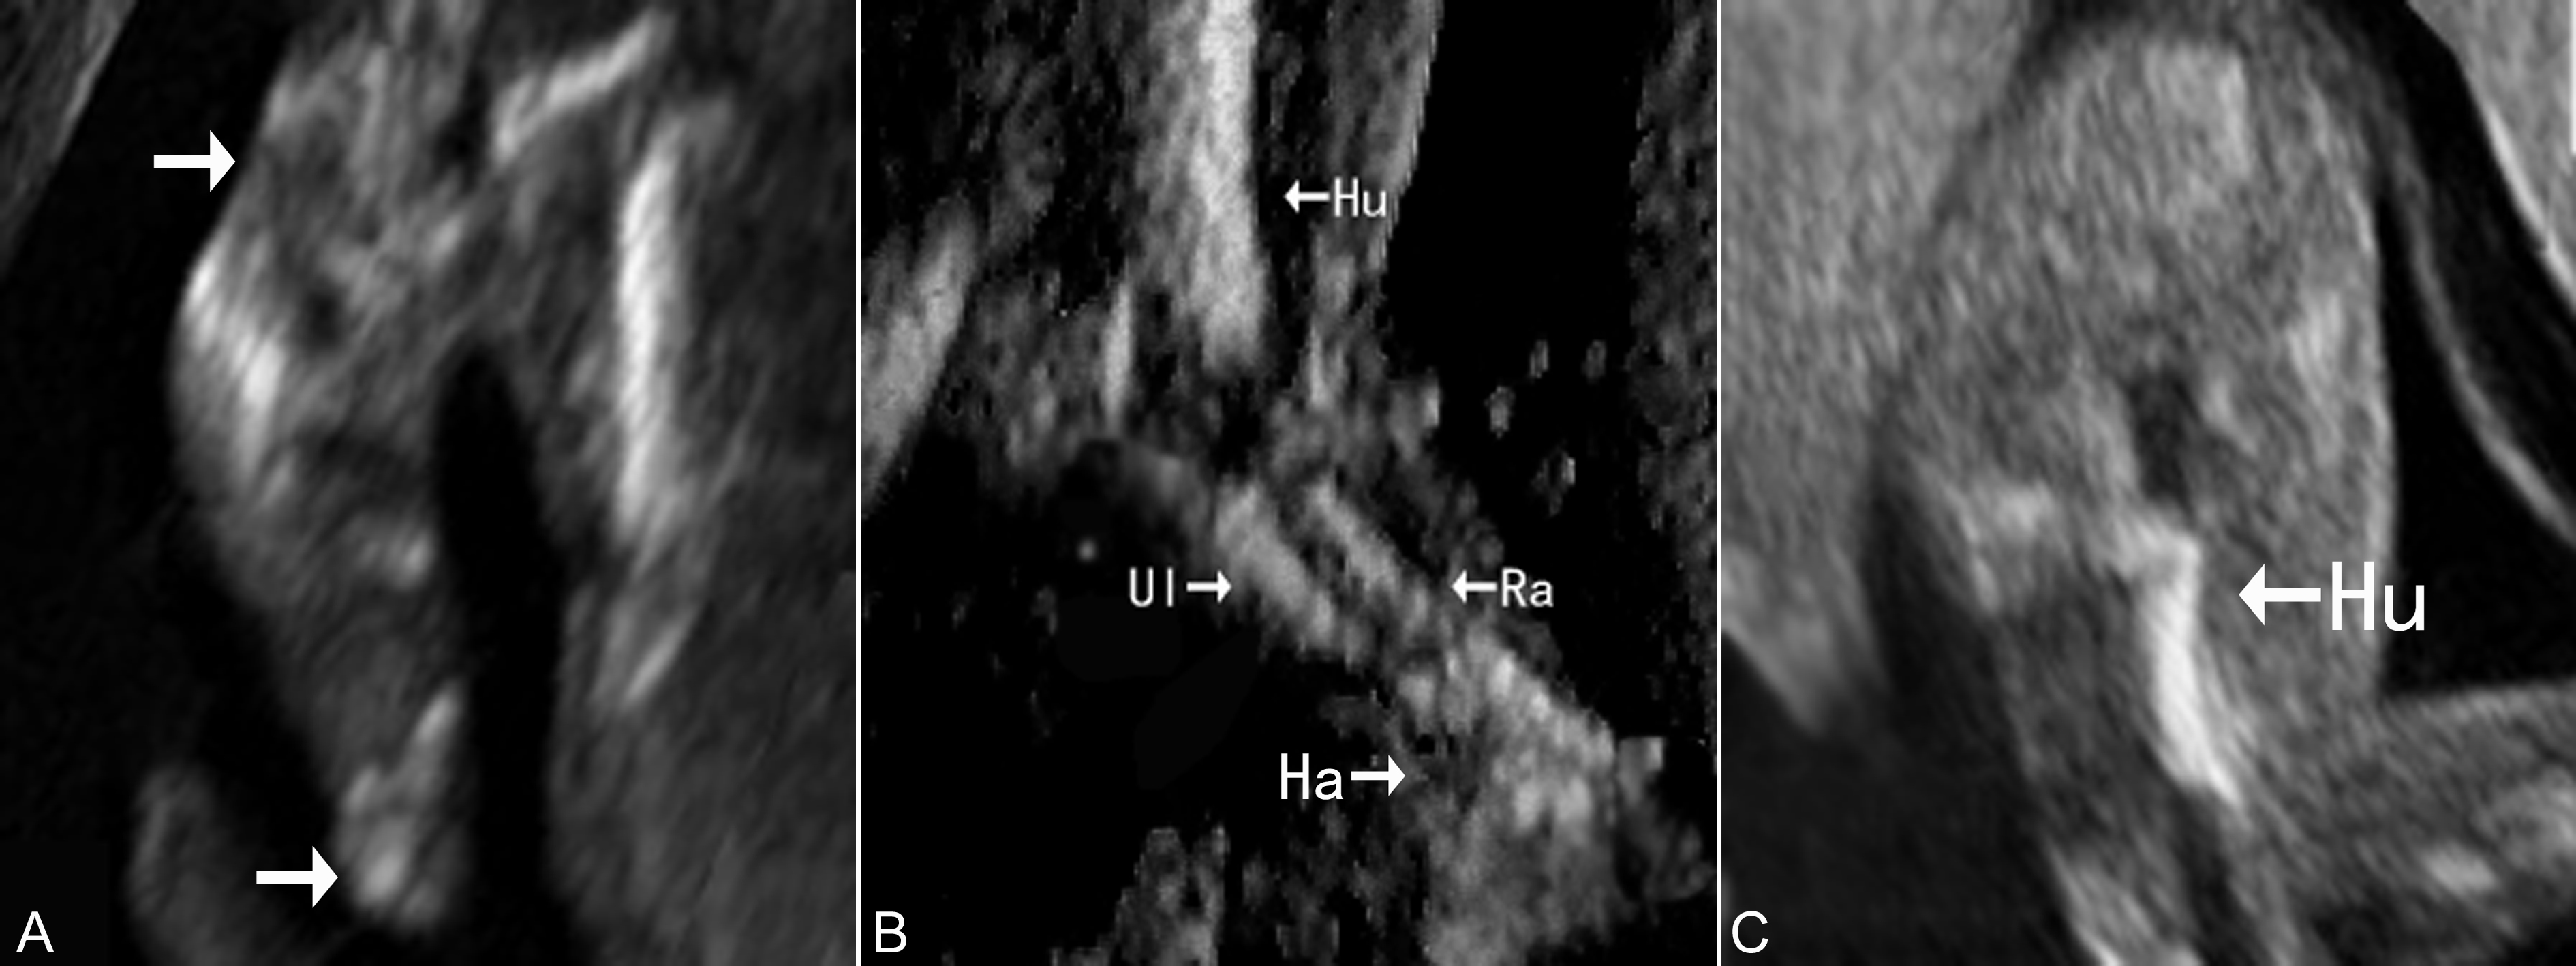

(1)长骨长度:发现肢体短小时要注意分辨短肢的类型,注意分辨为全段(所有部分)短肢畸形(图1A,图2A)、肢中部(中间部分)短肢畸形(图1B,图2B)、肢根性(近段部分)短肢畸形(图1C,图2C)和肢端部分(远端部分)短肢畸形。严重四肢全段短肢畸形(四肢长骨长度小于正常孕周平均值的4倍标准差、FL/AC<0.16)应警惕致死性骨骼发育异常。

图1胎儿四肢短小畸形分类:A:短肢畸形;B:中段畸形;C:近段畸形

图2胎儿上肢短小畸形:A:短肢并手部畸形;B:中段短肢(尺骨、挠骨);C:近段畸形